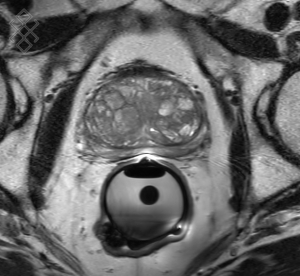

IRM Prostatique

La durée moyenne de l'examen est de 35 min. Dans le cas d'une injection, le manipulateur en radiologie vous administrera le produit de contraste. Vous entrendrez un bruit caractéristique à l'IRM faisant penser à un marteau piqueur. En début d'examen, pour limiter le péristaltisme, vous recevrez une injection d'un anti-spasmodique. Par ailleurs, l'introduction de la sonde rectale pourra être désagréable, mais pas douloureuse.